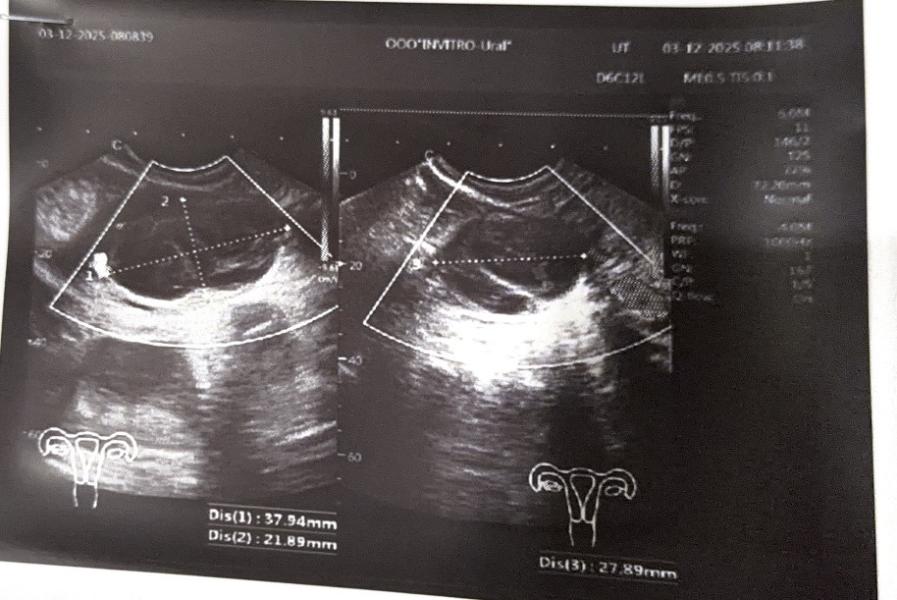

Сходила утром сегодня ещё раз на узи, образование выросло в два раза, про желтое тело ничего не написали, тут врач сказал, что очень похоже на кисту желтого тела размером 37х21х27 и ни слово про желтое тело, разве за ночь киста может увеличиться в два раза? Может вчера не было никакого жт, а просто это всё киста?

1 фото узи вчера, 2 фото узи сегодня